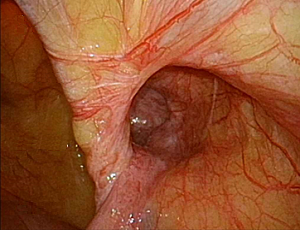

���`�ɂP�Omm�̌��������ē����������Ȃ��̒��ɑ}�����A���ǂɊJ�������i�w���j�A��j���m�F���A���b�V���V�[�g�����ɂ��Ăĕ����܂��B